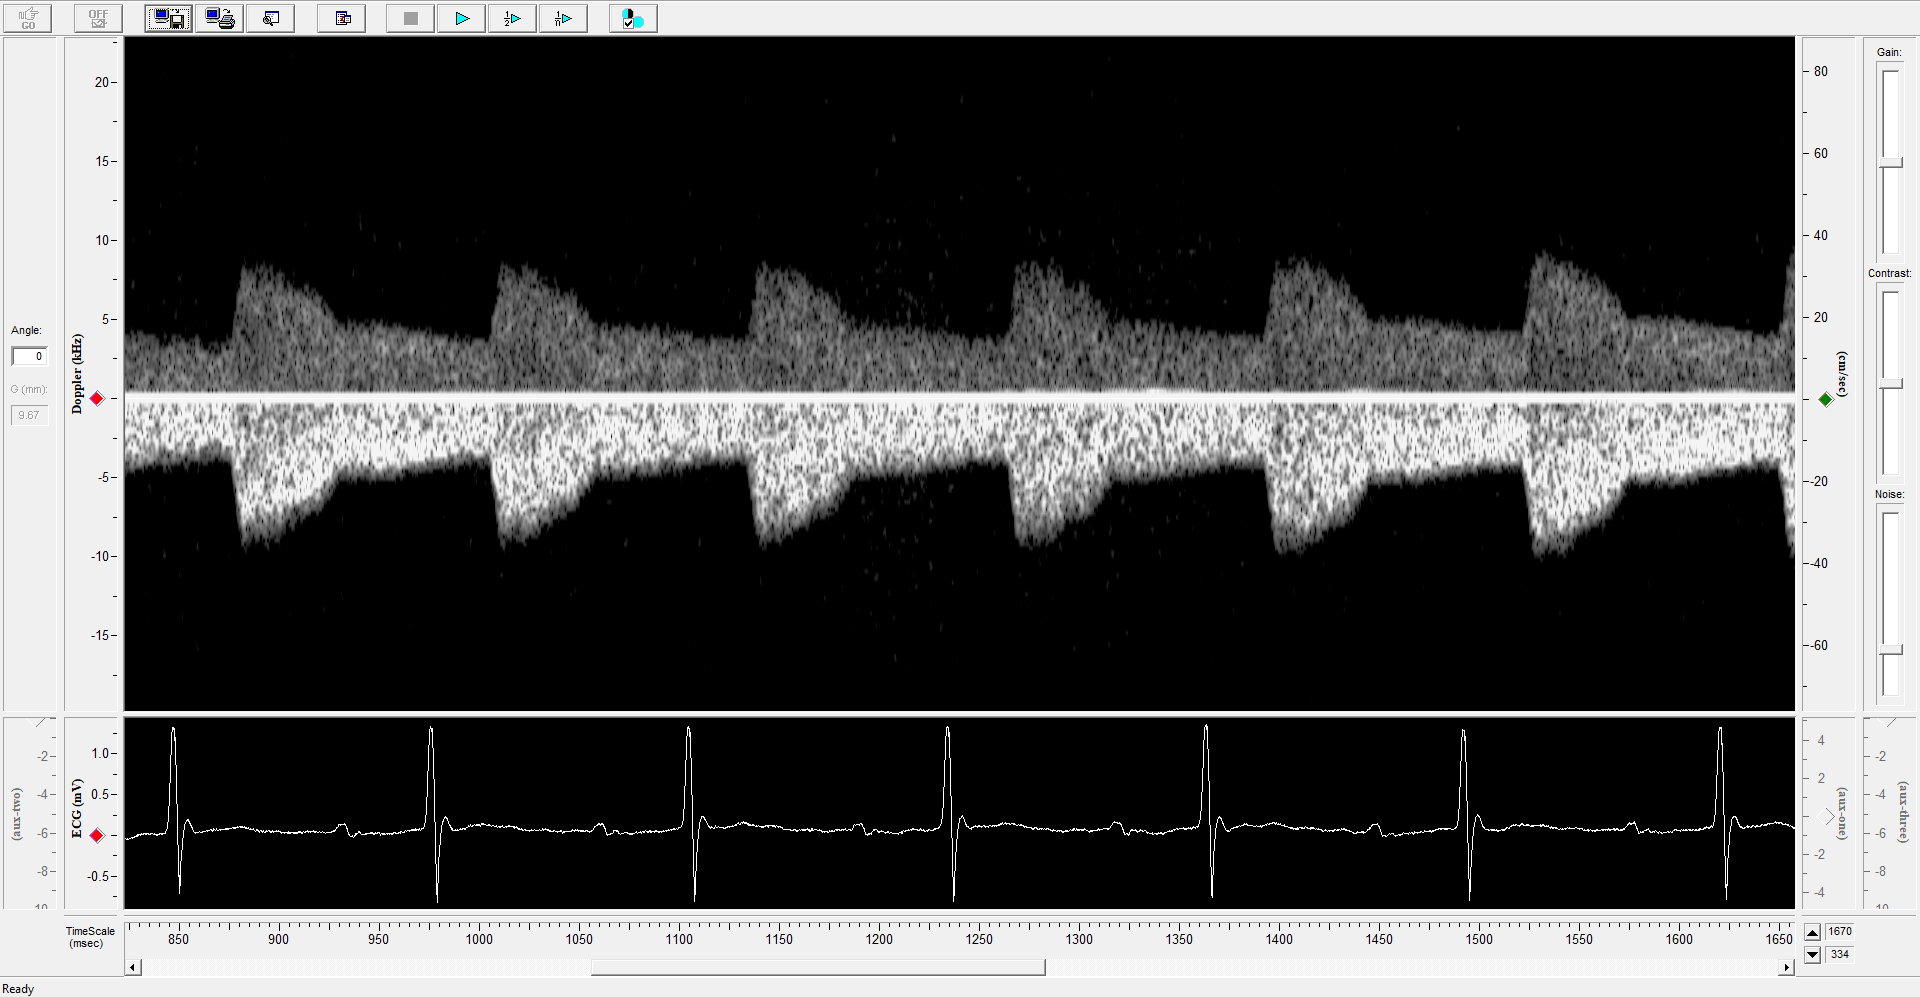

The Indus Doppler Flow Velocity System is a high-frequency, real-time pulsed Doppler measurement device with integrated data analysis software designed for measuring cardiovascular function in small animals. The high sampling rates grant excellent temporal resolution, making this the ideal system for studying fast heart rates and rapid blood accelerations present in small animals. Hardware components include the Pulsed Doppler Transceiver (PDT – a 10 & 20 MHz switchable dual channel system), Doppler Signal Digitizer (DSD), Doppler Workstation (DW), and handheld miniature probe(s).

Pulsed Doppler signals from the PDT are digitized at high sampling rates by the DSD and the workstation software. The acquired signals are processed using a fast Fourier transform algorithm and displayed as real-time grayscale Doppler flow velocity spectrograms. The workstation software permits recording and analysis of these spectrograms, ideal for report generation and publication purposes. This system has been successfully used in publications with mice, rats, bats, naked mole rats and other small animals. It is also capable of measuring blood flow velocities in larger animals using our implanted extra-vascular Doppler cuff probes.

- With dual-probe imaging, the DFVS allows simultaneous measurement at two vascular sites of interest in real-time, ensuring integrated and accurate vascular stiffness pulse wave velocity measurements.

- Flow velocity routinely measured from aortic arch, abdominal aorta, carotid artery, and/or femoral artery

Pulse Wave Wave Velocity